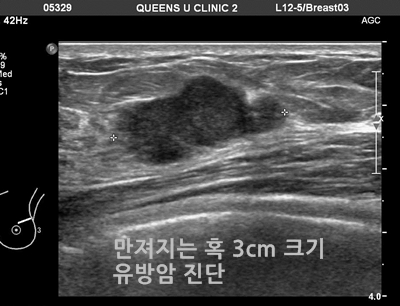

계적으로 여성은 3명 중 1명이 암에 걸린다고 합니다. 여성암 중 갑상선암 다음으로 두 번째로 높은 암이 유방암이라고 하는데, 중년 여성의 암 사망률로는 유방암이 1위라고 합니다. 유방암이란 유방에 나타나는 모든 악성 종양을 통틀어 말하는 것으로 보입니다. 유방암은 유방에 비정상적인 조직이 계속 자라거나 다른 장기에 퍼지는 위험한 병이라고 할 수 있습니다.